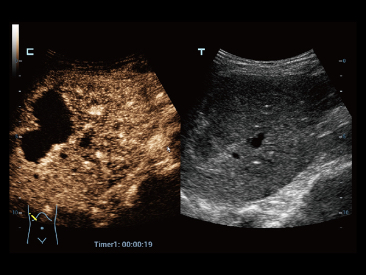

Sinds de oprichting van het bedrijf is Mindray voortdurend op zoek naar nieuwe manieren om het diagnostisch vertrouwen te vergroten. Resona 7 wordt aangestuurd door de meest revolutionaire ZONE Sonography?-technologie. Zijn nieuwe ZST+-tilt de kwaliteit van ultrasoundbeeldvorming naar een hoger niveau door middel van zoneacquisitie en kanaalgegevensverwerking.

Naast de hoogwaardige beeldvormingskwaliteit verbetert de Resona 7 tevens de klinische onderzoeksmogelijkheden met de revolutionaire V Flow voor vasculaire hemodynamische evaluatie, en de intelligentste vlakacquisitie van een 3D-gegevenssets voor de diagnose van het foetale, centrale zenuwstelsel. Met zijn combinatie van de meest intu?tieve, op vingerbewegingen gebaseerde multi-aanrakingsbediening en alle essenti?le klinische functies loopt de Resona 7 voorop in de nieuwe golven van ultrasoundinnovatie.